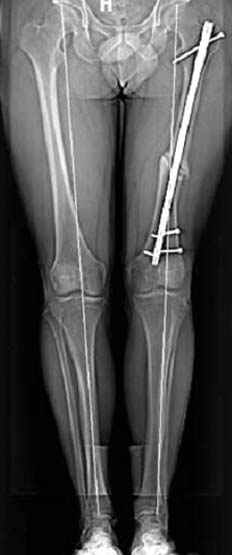

5:24 Рентгенограмма таза, вызывают врача ортопеда (снимок N1), его диагноз: закрытый переломо-вывих правого тазабедренного сустава, получает добро на закрытую репозицию в приемном отделении

N 2

сустава, репозиция вывиха (N4), фиксация фрагмента 2.7(4) мм шурупами и допольнительно реконструктивной пластиной на 8 дырок, фиксация 3.5мм шурупами проксимально и дистально.

Интраоперционные N5 косая запирательная и N6 подвздошный снимок

11:50 больной в послеоперационной, рентгенограмма N7, компьютерная томограмма в тот же день N8-10

На рисунке N1 предоперационный план лечения ложного сустава шейки бедра- линия ложного сустава, угол и направление введения импланта, клиновидная остеотомия в градусах и миллиметрах, второй снимок после коррекции, расчет, на сколько удлиняется конечность и размеры импланта;

N3 рисунок окончательный снимок, после операции моя рентгенограмма должен выглядеть примерно как эта картина. На N4 снимке клин перед удалением; N5 послеоперации 3 нед.; N6 окончательная рентгенограмма.

варус при проксимальном отделе 95 градусной пластиной.